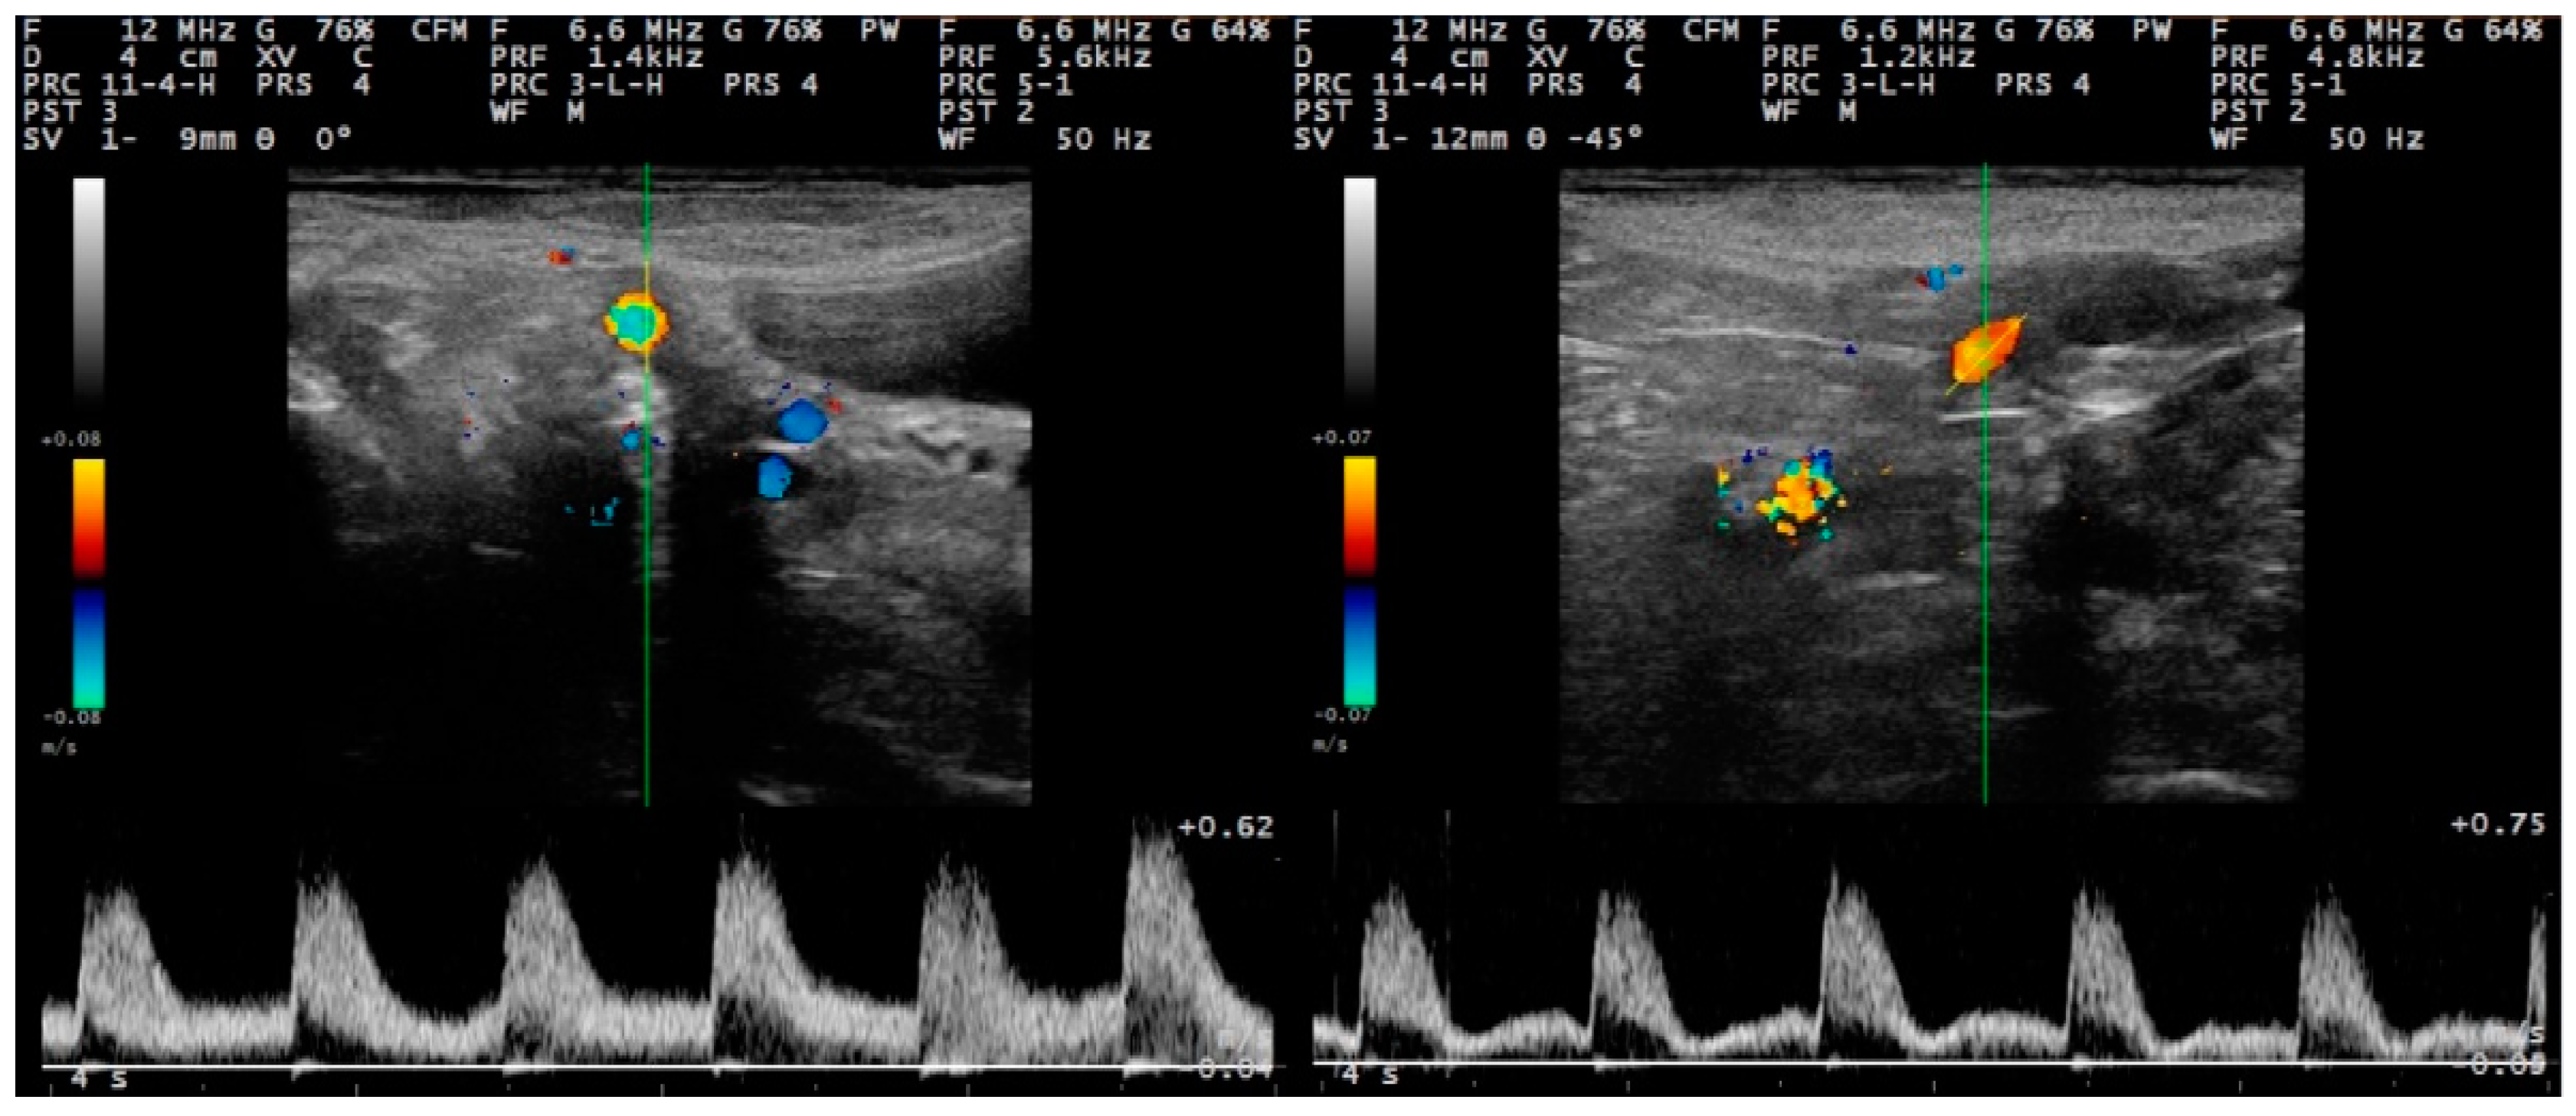

2.2.2. Doppler Mode Examination

The spectral display in Doppler mode was observed as a broad band structure (Figure 3 and Figure 4). The diameter of the uterine artery was similar in the two groups on S1, but thereafter remained significantly larger in group I ewes (p < 0.02). The resistance and pulsatility indexes remained smaller in the group I ewes throughout the study, whilst the blood pressure was higher in these ewes. Finally, blood flow volume into the uterus was significantly higher in group I ewes after challenge (p < 0.02) (Table 4). Moreover, for both groups, the progressive changes in the haemodynamic parameters (except for blood velocity) were significant (Table 4).

For all measurements taken after challenge, the uterine artery diameter and the blood flow volume into the uterus were significantly greater in I than in C ewes: 0.31 ± 0.01 cm versus 0.27 ± 0.01 cm (p = 0.008) and 92.7 ± 7.2 mL min−1 versus 62.0 ± 5.3 mL min−1 (p = 0.032), respectively (Figure 5). For the other haemodynamic parameters evaluated, no significant differences were evident (p > 0.20).

Figure 3. Sequential post-partum spectral waveforms of the uterine artery (Doppler ultrasonography) of ewes with experimentally induced uterine infection (group I), left to right: D2 and D12 (images taken and processed on a MyLab® 30 ultrasonography system with linear transducer, Doppler imaging frequency: 6.6 MHz; scanning depth: 40 mm) (D0: day of inoculation).

Figure 4. Sequential post-partum spectral waveforms of the uterine artery (Doppler ultrasonography) of normally involuting ewes (uninoculated controls) (group C), left to right: D2 and D12 (images taken and processed on a MyLab® 30 ultrasonography system with linear transducer, Doppler imaging frequency: 6.6 MHz; scanning depth: 40 mm) (D0: day of inoculation).